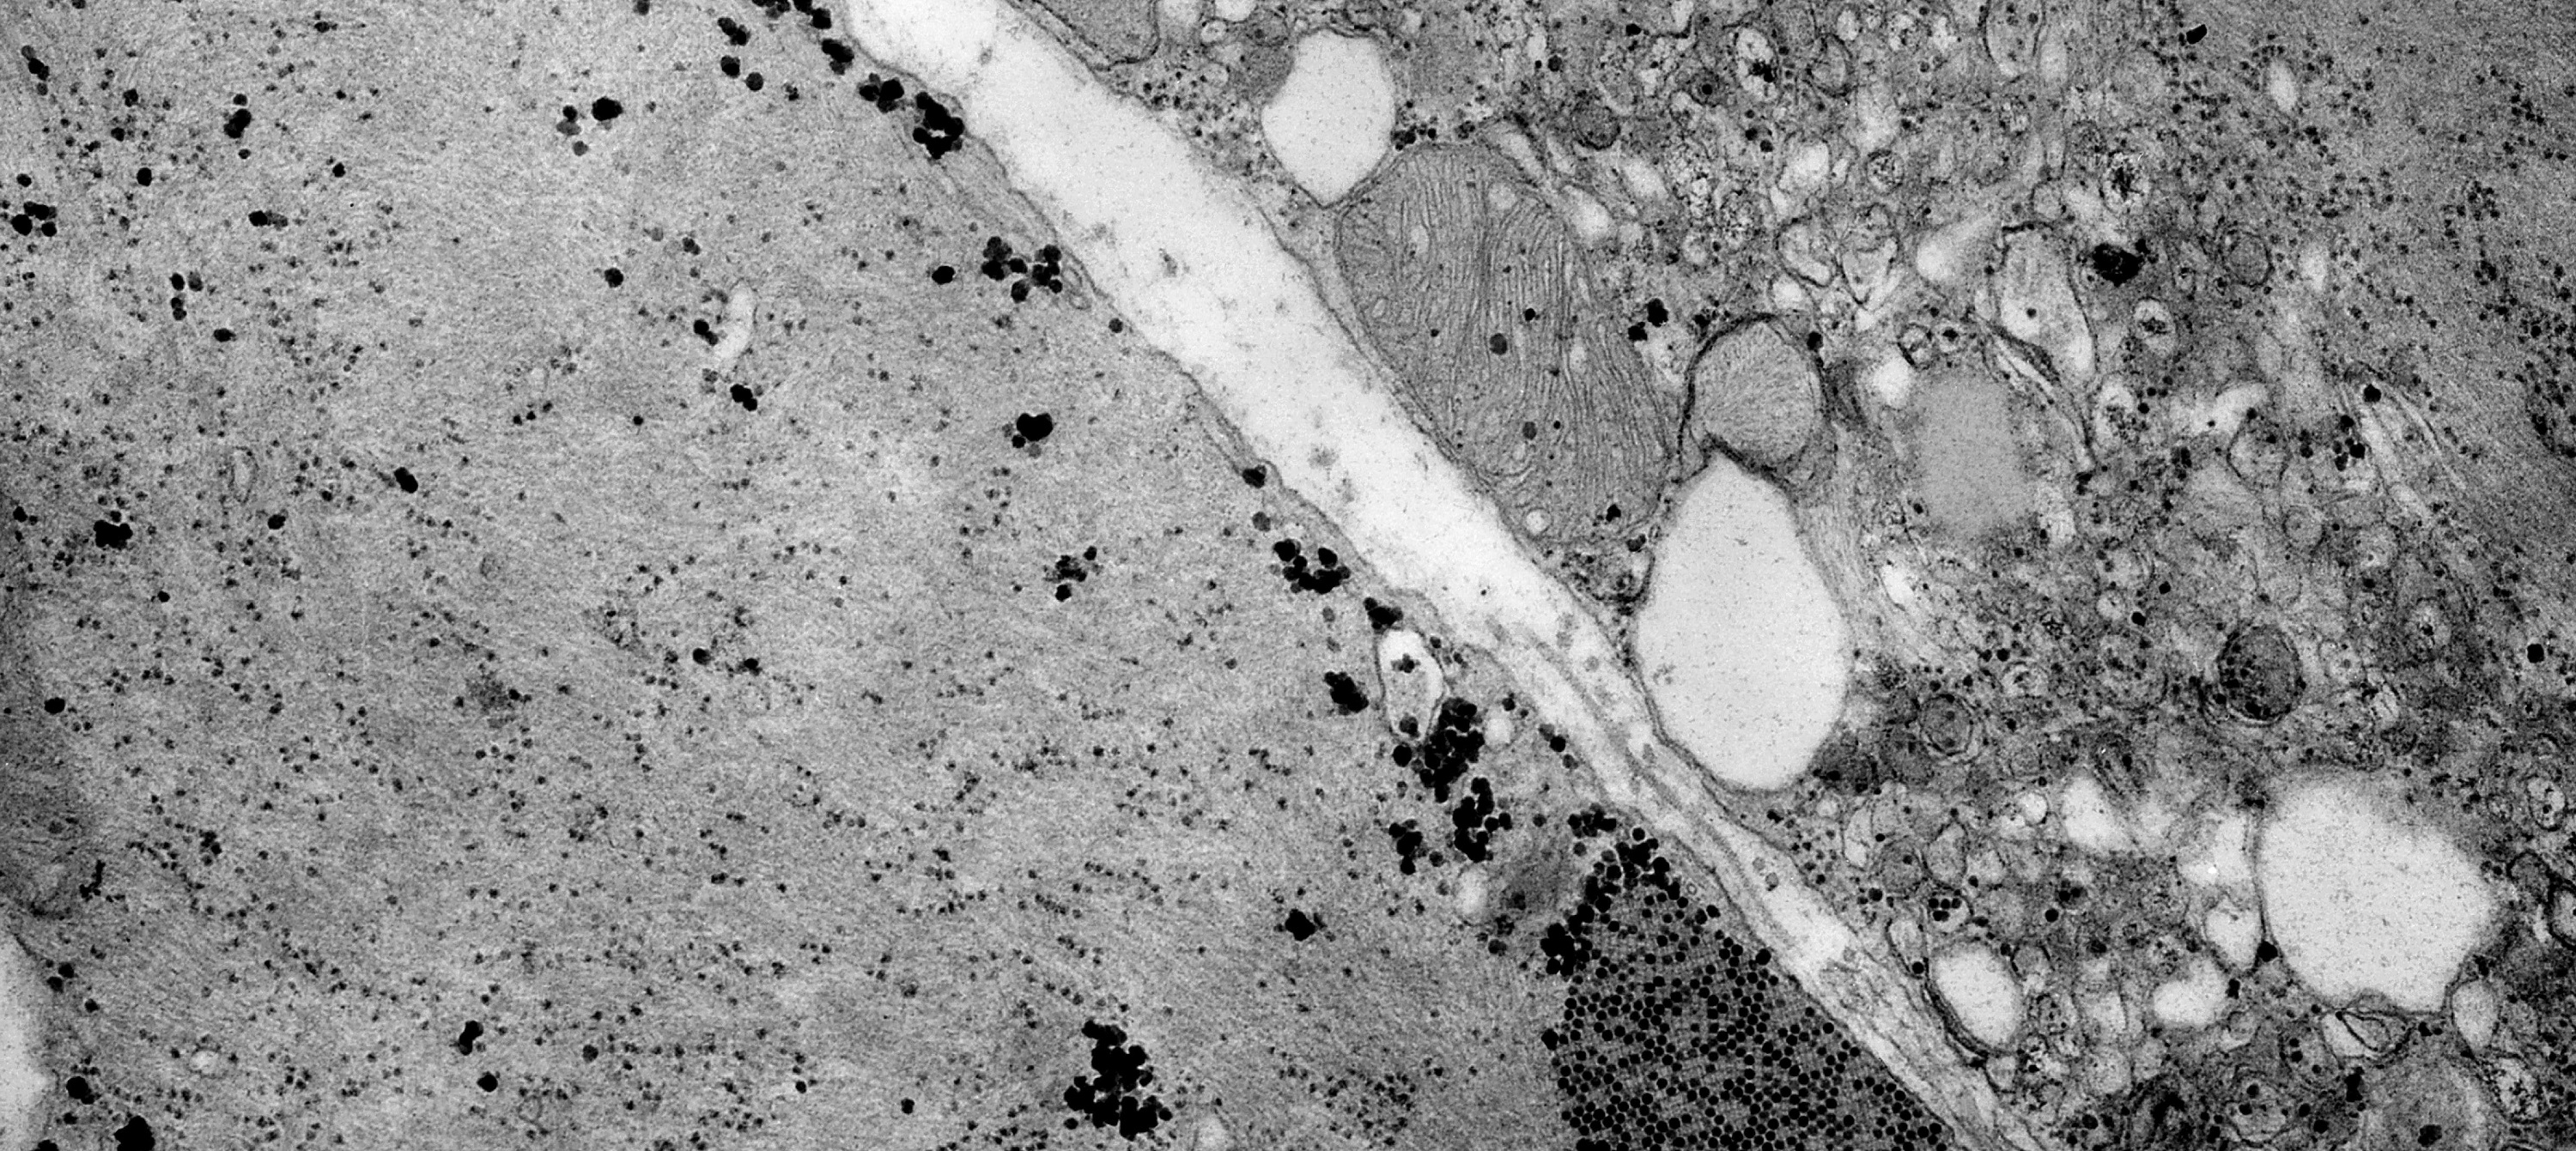

Proponen prevenir el daño oxidativo mitocondrial como diana terapéutica de la enfermedad de Charcot-Marie-Tooth

21/07/2021